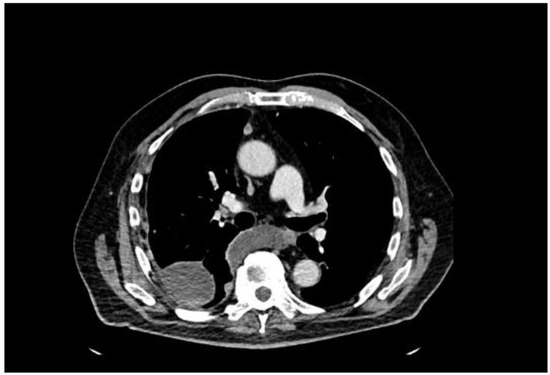

A 77-year-old man presented with several weeks of exertional dyspnea and intermittent dry cough. His past medical history was notable for ankylosing spondylitis, chronic gastritis, a left salivary gland tumor resected 11 years prior (pathologic details unknown), and a cholecystectomy. He had a significant smoking history (20 pack-years) but quit 32 years earlier. An initial chest radiograph, obtained to evaluate possible heart failure, revealed a large right-sided pleural effusion. Figure 1 A contrast-enhanced computed tomography (CT) of the chest further delineated multiple pleural nodules (up to 17 mm) and diffuse, bilateral small pulmonary nodules. Figure 2 and Figure 3 Two thoracenteses drained ~3800 mL of hemorrhagic pleural fluid in total. Fluid cytology was negative for malignancy, and no cell block preparation was performed. Further evaluation with bronchoscopy and bronchoalveolar lavage was unremarkable for infection or malignant cells.

Figure 2. CT—axial plane, after contrast administration, right-sided effusion, small enhancing after contrast administration pleural nodules.